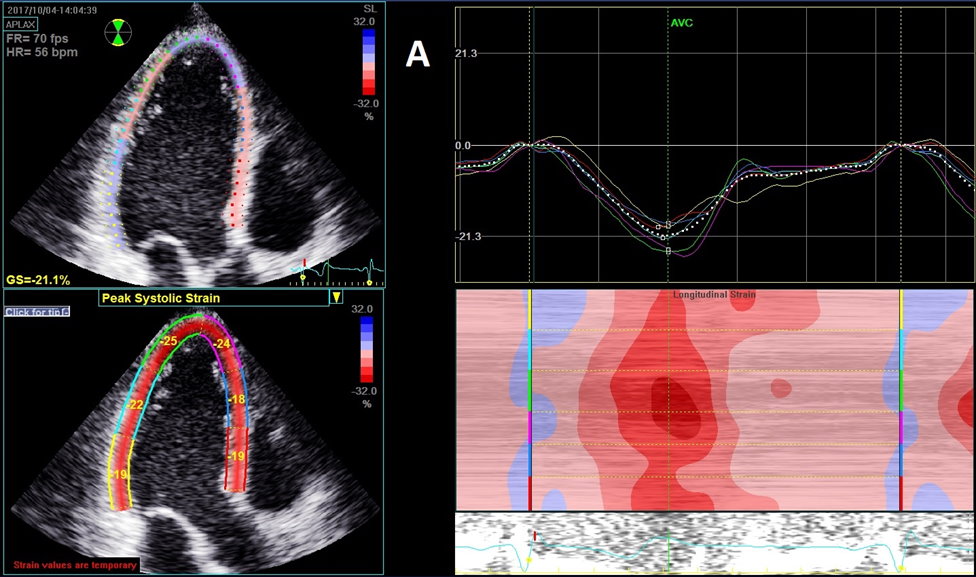

Strain Imaging in Echocardiography Part 3: Cardiac Pathology and Patterns of Strain